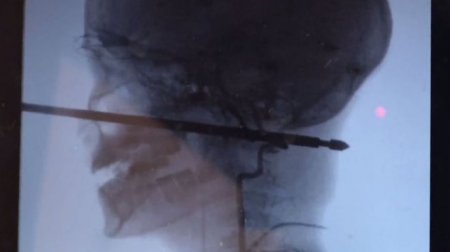

Мальчик играл в доме, закрепленном на стволах деревьев, когда на него напали осы. Он свалился с высоты чуть более метра и приземлился прямо на 30-сантиметровый металлический шампур для приготовления шашлыков. Шампур пронзил череп и погрузился в ткани головы на 15 сантиметров. К счастью, чудесным образом металлическая палка вошла в голову, миновав и глаза, и мозг, и спинной мозг, и крупные кровеносные сосуды.

Так как из раны не было активного кровотечения и шампур не повредил жизненно важные органы, врачи успешно удалили квадратный стержень. Операция была очень сложной именно из-за формы шампура с острыми краями и длилась несколько часов.

Коджи Эберсоул, директор отделения эндоваскулярной нейрохирургии больницы Университета Канзаса сказал Kansas City Star, что самую большую сложность для хирургов при удалении шампура представляли кровеносные сосуды на шее мальчика. Врач назвал чудом то, что при такой сквозной травме шампур не повредил ничего в голове потерпевшего роковым образом.